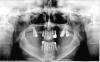

Nebel Опубликовано 3 августа, 2012 Поделиться Опубликовано 3 августа, 2012 Скажите, пожалуйста, можно ли при такой кости ставить импланты? Записалась к врачу на установку имплантов, но позже другой врач сказал, что кость не подходит для этой процедуры ввиду выраженной атрофии. Ссылка на комментарий

IvanK Опубликовано 3 августа, 2012 Поделиться Опубликовано 3 августа, 2012 (изменено) Решает все ортопед, накрутить можно куда и как угодно, но ведь не в этом цель. Цель - протезирование с опорой на имплантатах, чтоб Вы могли ими долго и счастливо грызть яблоки Судя по снимку, в данных условиях поставить имплантаты в правильные ортопедические позиции невозможно.До любых манипуляций необходима санация полости рта (вылечить то, что нужно лечить, удалить то, что нужно удалить) Изменено 3 августа, 2012 пользователем IvanK Ссылка на комментарий

Bier Опубликовано 3 августа, 2012 Поделиться Опубликовано 3 августа, 2012 только по этому снимку не определить где надо, надо ли и сколько наращивать. т.к. снимок этот двухмерный, а мы с вами и имплантаты в том числе - трехмерные ) Ссылка на комментарий

Dr. Surkin Опубликовано 4 августа, 2012 Поделиться Опубликовано 4 августа, 2012 только по этому снимку не определить где надо, надо ли и сколько наращивать. т.к. снимок этот двухмерный, а мы с вами и имплантаты в том числе - трехмерные ) +1 В современных условиях планировать установку имплантатов следует с использованием данных компьютерной томографии. 1 Ссылка на комментарий